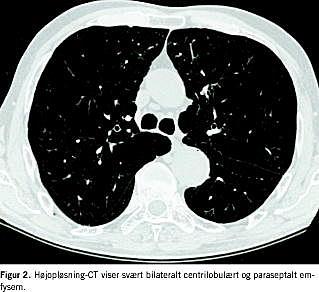

Fem måneder senere blev patienten henvist med vedvarende funktionsdyspnø. Han havde fået budesonid, terbutalin og tiotropiuminhalationer uden mærkbar forbedring. Lungefunktionen (LFU) var kun let obstruktiv med svært nedsat diffusion (FEV1 2,1 l (72%), FEV1 /FVC 55%, total lungekapacitet (TLC) 6,3 l (94%), residualvolumen (RV) 2,4 l (96%) og DL CO 1,2 mmol/min/kPa (13%)), der gav mistanke om lungeemboli. Ventilation-perfusions-scintigrafi viste tydelig perfusionsdefekt i venstre overlap med bevaret ventilation (Figur 1 ), hvilket er foreneligt med lungeembolus. Denne usikkerhed i diagnosen søgtes afklaret ved HRCT, som viste svære udbredte emfysematiske forandringer, der er i overensstemmelse med centrilobulært og paraseptalt emfysem bilateralt (Figur 2 ).

HRCT har en høj sensitivitet og specificitet ved emfysem [1]. Det karakteristiske radiologiske fund er områder med lav attenuation, som ved centrilobulært emfysem grupperes centralt i den sekundære lobulus omkranset af normalt lungevæv (Figur 2). Disse områder er den radiologiske ækvivalent til de patologiske forandringer. CT's anden fordel er udelukkelse af ledsagende lungesygdomme. Rygning er ikke alene en risikofaktor for emfysem, men også for lungekræft og interstitielle lungesygdomme, hvor CT spiller en central rolle i udredningen.